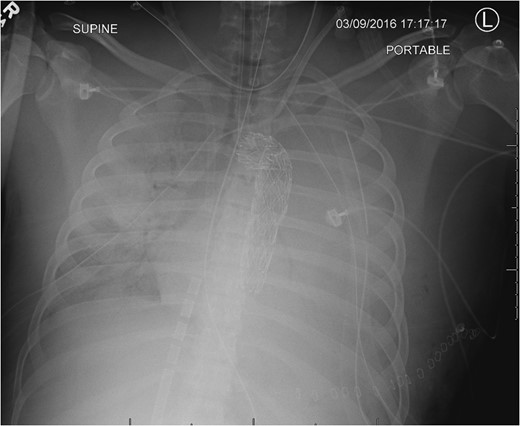

Admission AP CXR demonstrating a widened mediastinum and increased haziness of the left hemi-thorax.

During the abdominal exploration, multiple mesenteric injuries were identified and repaired. An abbreviated damage control laparotomy with packing was performed. A left-sided chest tube was inserted and drained ~800 ml of blood without continued hemorrhage.